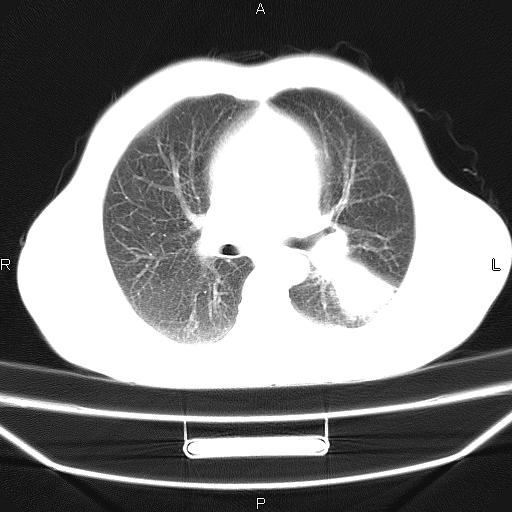

患者,男,40岁。间断发热,咳嗽二十余日。体温最高达38.9° 在当地诊所抗炎治疗三天后体温降至正常,患者自行停药。今又发热。胸片示,左下肺阴影。

左下肺片状高密度影,境界模糊,密度不均,考虑感染性病变可能性大,建议抗炎治疗后复查。左肺门增大,不除外占位性病变,必要时支气管镜检。